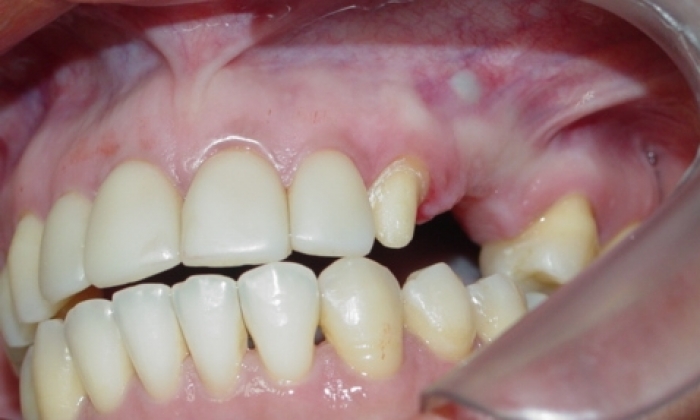

Próteses fixas de porcelana instaladas